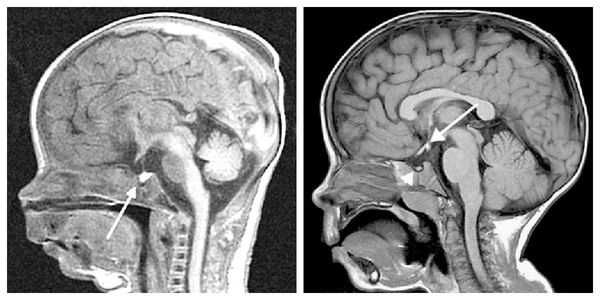

Нейровизуализацию опухоли гипофиза позволяет осуществить рентгенография черепа и зоны турецкого седла, МРТ и КТ головного мозга. Рентгенологически могут определяться увеличение размеров турецкого седла и эрозия его дна, а также увеличение нижней челюсти и пазух носа, утолщение костей черепа, и расширение межзубных промежутков. С помощью МРТ головного мозга возможно увидеть опухоли гипофиза диаметром менее 5 мм. Компьютерная томография подтверждает наличие аденомы и ее точные размеры.

Для выявления опухолей гипофиза проводится рентгенография черепа, КТ и МРТ головного мозга. При наличии аденомы гипофиза определяется увеличенное турецкое седло (ложе гипофиза). Рентгенограммы кистей рук показывают несоответствие между костным и паспортным возрастом. При офтальмологическом обследовании пациентов с гигантизмом выявляется ограничение зрительных полей, застойные явления в глазном дне.

При необходимости проводится МРТ головного мозга и гипофиза с контрастированием [6] . Она позволяет исключить или подтвердить наличие объёмных образований области гипофиза и головного мозга.

- Наличие аденомы гипофиза при проведении компьютерной, либо магнитно-резонансной томографии с контрастированием.